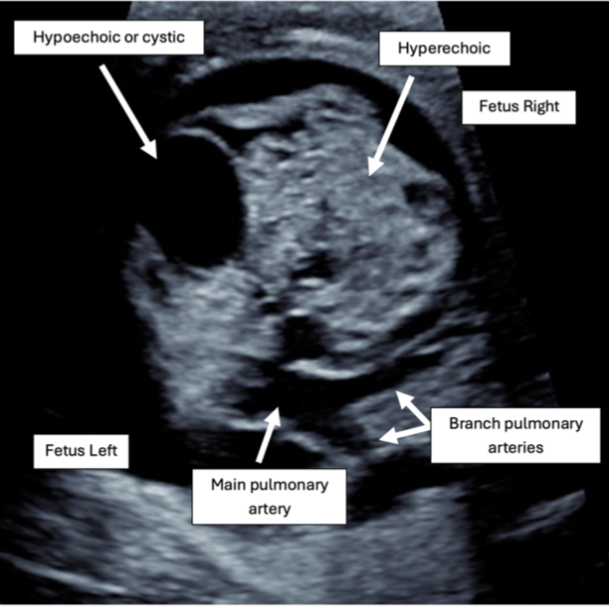

This fetus has a large, solitary, heterogeneous pericardial mass and a large pericardial effusion. Labeled frames from Video 1 are shown in Figures 1 and 2. These findings are characteristic of fetal teratomas.

Figure 2: 2D Imaging in an Axial Plane Demonstrating a Large, Right-Sided Pericardial Mass With Heterogeneous Echogenicity

The MPA and branch PAs are seen without impingement by the tumor.

2D = two-dimensional; MPA = main pulmonary artery; PAs = pulmonary arteries.